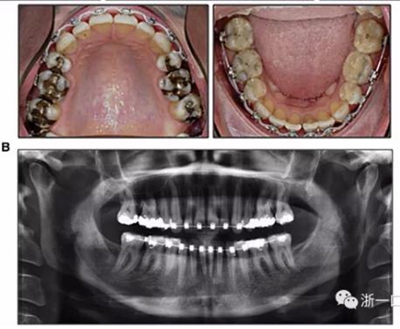

擴弓保持8周后,除擴弓器影響牙外粘接托槽,使用0.014鎳鈦絲進行排齊、整平。旋轉停止后3個月拆除擴弓器,全口粘接托槽,使用0.016niti繼續(xù)排齊整平。佩戴可摘保持器,保持上頜寬度。在使用至0.018x0.018niti7周,徹底排齊整平后,使用大弓型的0.016x0.022不銹鋼絲,繼續(xù)維持原有寬度,同時停止使用可摘保持器。掛II類牽,糾正磨牙關系,使用鏈圈關閉散在間隙,少量使用IPR去除局部前牙的黑三角。術后9個月拍全景示,牙根平行度可,再無其他牙根出現問題。1年7個月后治療結束。上下頜3-3舌側保持器+哈雷氏保持器進行保持。

治療結果:

患者側貌改善,下唇唇肌緊張消失,上下唇可自然閉合。磨牙及尖牙關系糾正至I類,覆合覆蓋正常。上下頜弓型糾正至卵圓形,牙弓寬度增加。頭影測量分析示SNA角81.8°,ANB角3°。頭影測量重疊圖示下頜骨向后旋轉,垂直面高度略有增加。